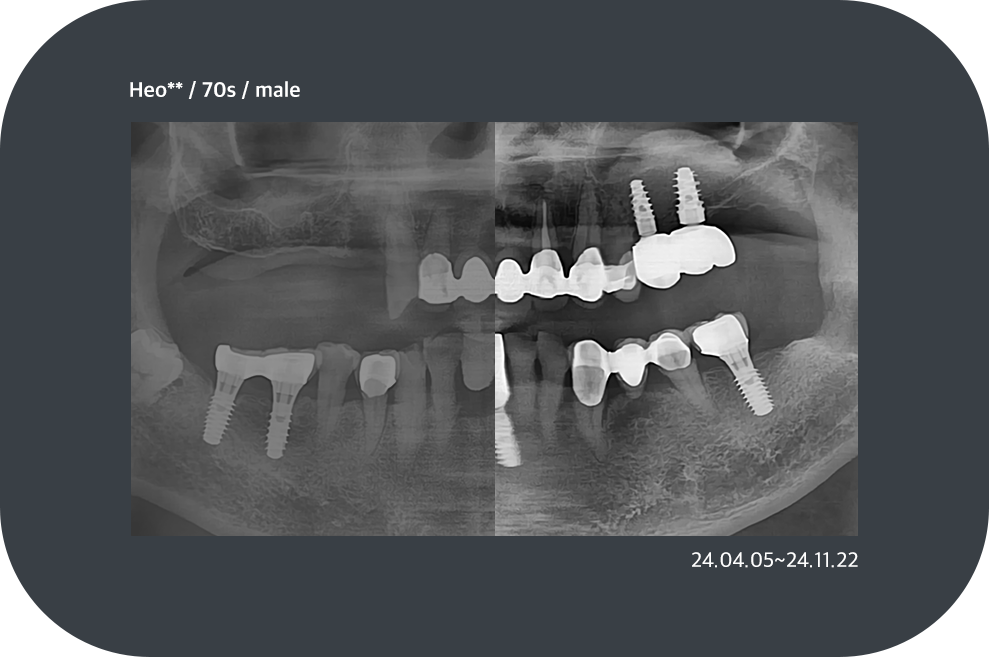

치료사례

임플란트 치료사례

implant_case01

implant_case02

implant_case03

implant_case04

*모든 증례 사진은 의료법 제23조, 제56조에 의거하여, 당사자의 동의하에 게시하였습니다.

*치료 사진은 모두 본원에서 치료한 환자분의 사진입니다.

*치료 사진은 모두 동일인의 사진이며, 동일조건에서 촬영하였습니다.

*개인의 차이에 따라 시술 및 수술 후 부작용이 발생할 수 있으며, 의료진과 충분한 상담을 받으시기 바랍니다.